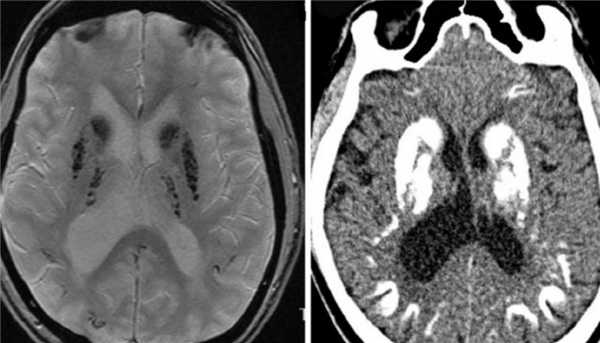

Гипертрофическая дегенерация ядер оливы считается специфической формой транссинаптической гипертрофической дегенерации и развивается вследствие неспецифического повреждения денто-рубро-оливарного пути. Хотя это состояние у детей считается редким, сообщается о его превалировании у пациентов с метаболическими заболеваниями, а также после операции по поводу опухолей задней черепной ямки. На МРТ выявляются Т2-гиперинтенсивные очаги, часто с билатеральным и симметричным увеличением оливарных ядер. Они начинают появляться в течение месяца после острого события и в течение 3-4 лет имеют тенденцию к разрешению.

К посттравматическим изменениям можно отнести гипертрофическую дегенерацию оливкового ядра, которая наблюдается крайне редко чрез 3-6 месяцев после травмы. При МРТ головного мозга выявляется повышенный сигнал на Т2-взвешенных МРТ с одной или двух сторон.

МРТ головного мозга. Т2-взвешенная аксиальная МРТ. Гипертрофическая дегенерация левого оливкового ядра.